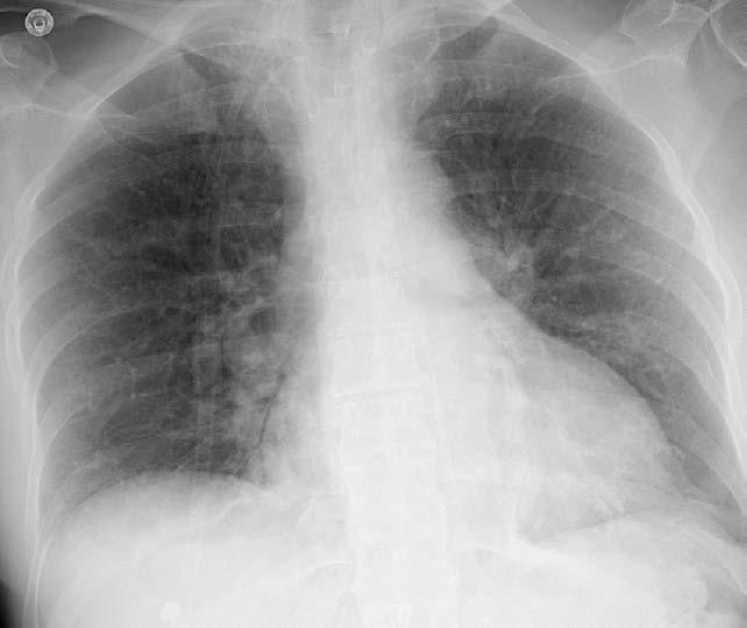

Figure 2: Common chest x-ray projections.

(a) P-A

Refer to caption

(b) Decubit

Figure 4: Pleural effusion in different projections: A bipedestation projection (a) shows the meniscus sign in which the fluid accumulates in the subpulmonary region, ascends through the thoracic wall and through the paramedian zone. In decubit projection (b) there is no meniscus sign. As the liquid goes to the most declining area there is a diffuse increase in hemithorax density and a loss of the net limit of the diaphragm with occupation of the pulmonary vertex by apical cap, costo-phrenic angle blunting and a thickening of the smaller fissure.

The projection information is highly relevant for diagnosis. For example, AP views, which are commonly used in pediatric patients, show an enlarged heart silhouette (Fig. 2(j)) that should not be interpreted as cardiomegaly, but merely the expected large-depth ratio of reversed organ observation (Fig. 3). Another illustrative example is the distinct pattern that pleural effusions have in the standing position (Fig. 4(a)), in which a typical meniscus sign is commonly found as opposed to decubit projections (Fig. 4(b)). Given that the number of different projections is unbalanced (for instance, PA followed by lateral projections typically comprise the majority of chest x-rays), there is the risk that none of the other projections will have sufficient instances with which to train models capable of discriminating pathological from non-pathological patterns in the context of the projection.